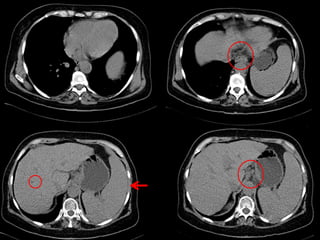

 Hallazgos Radiológicos:

 Irregularidad de contornos hepáticos

 Hipertensión portal

 Varices esofágicas

 Esplenomegalia

Daño hepático crónico

Terminado el examen… Protocolo Aplicado  DHC  Hepatocarcinoma  Rendimiento del método:  Caracterización de lesiones  Control de quistes  Control preoperatorio  Respecto a la Patología:  Protocolo adecuado  Hallazgos Radiológicos:  Irregularidad de contornos hepáticos  Hipertensión portal  Varices esofágicas  Esplenomegalia